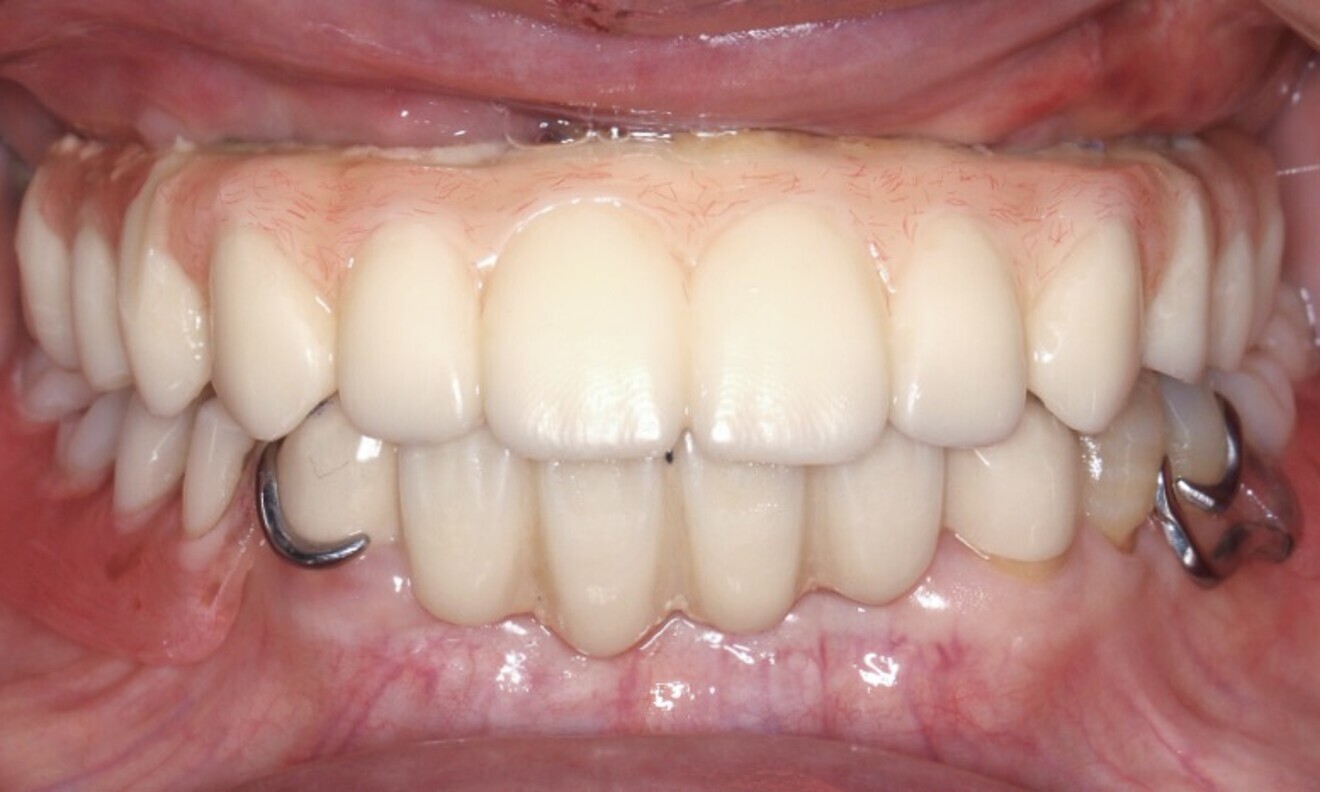

After 12 weeks, the delivery of the final screw-retained prosthesis was performed. During this time, the implant sites healed successfully, and osseointegration was accomplished.

An open-tray impression was taken, leading to the acquisition of the final cast models. These models were then utilised to create the final prosthesis. A comprehensive assessment was conducted of the prosthesis to ensure a precise and passive fit during the clinical evaluation. Furthermore, functionality, phonetics, occlusion and aesthetics were meticulously verified (Fig. 13). The screw access holes were filled using Filtek Supreme resin (3M ESPE). Oral hygiene instructions were given, and periodontal supportive therapy was scheduled for every three to four months.